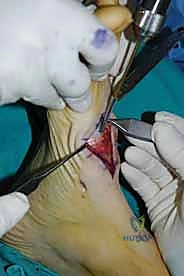

4. تصحيح التشوه (Deformity Correction)

إذا كان هناك تسطح في القدم أو هبوط في القوس، يقوم الدكتور هطيف بإعادة ترتيب العظام في وضعها التشريحي الصحيح لاستعادة قوس القدم الطبيعي.